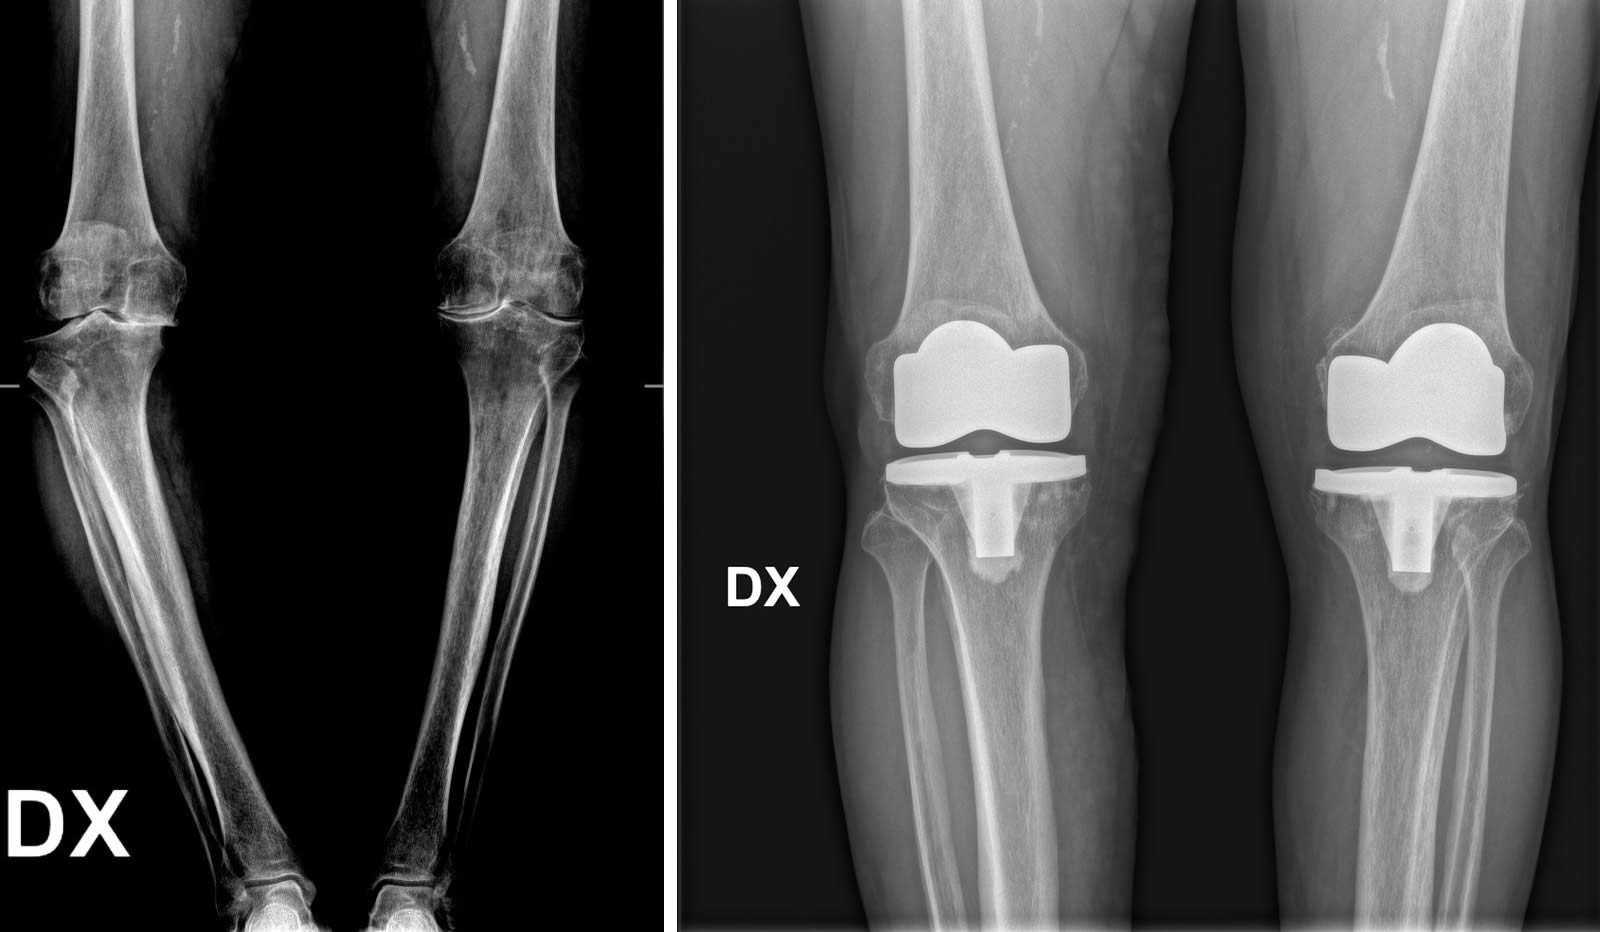

Prima e dopo l'intervento

Per formulare una diagnosi corretta e ottenere un quadro clinico completo del paziente, è fondamentale eseguire una radiografia (RX) del bacino o bilaterale ginocchio in carico ovvero in piedi.

Quando si prende in considerazione la protesi al ginocchio, si aprono diverse possibilità di intervento. È possibile optare per soluzioni mini-invasive che prevedono l'inserimento di protesi monocompartimentali, adatte a sostituire solo una parte dell'articolazione, oppure per protesi parziali o totali, in base alle esigenze e alla gravità della situazione. La scelta dell’intervento viene valutata attentamente dal chirurgo, mirando sempre a garantire il miglior recupero funzionale possibile.